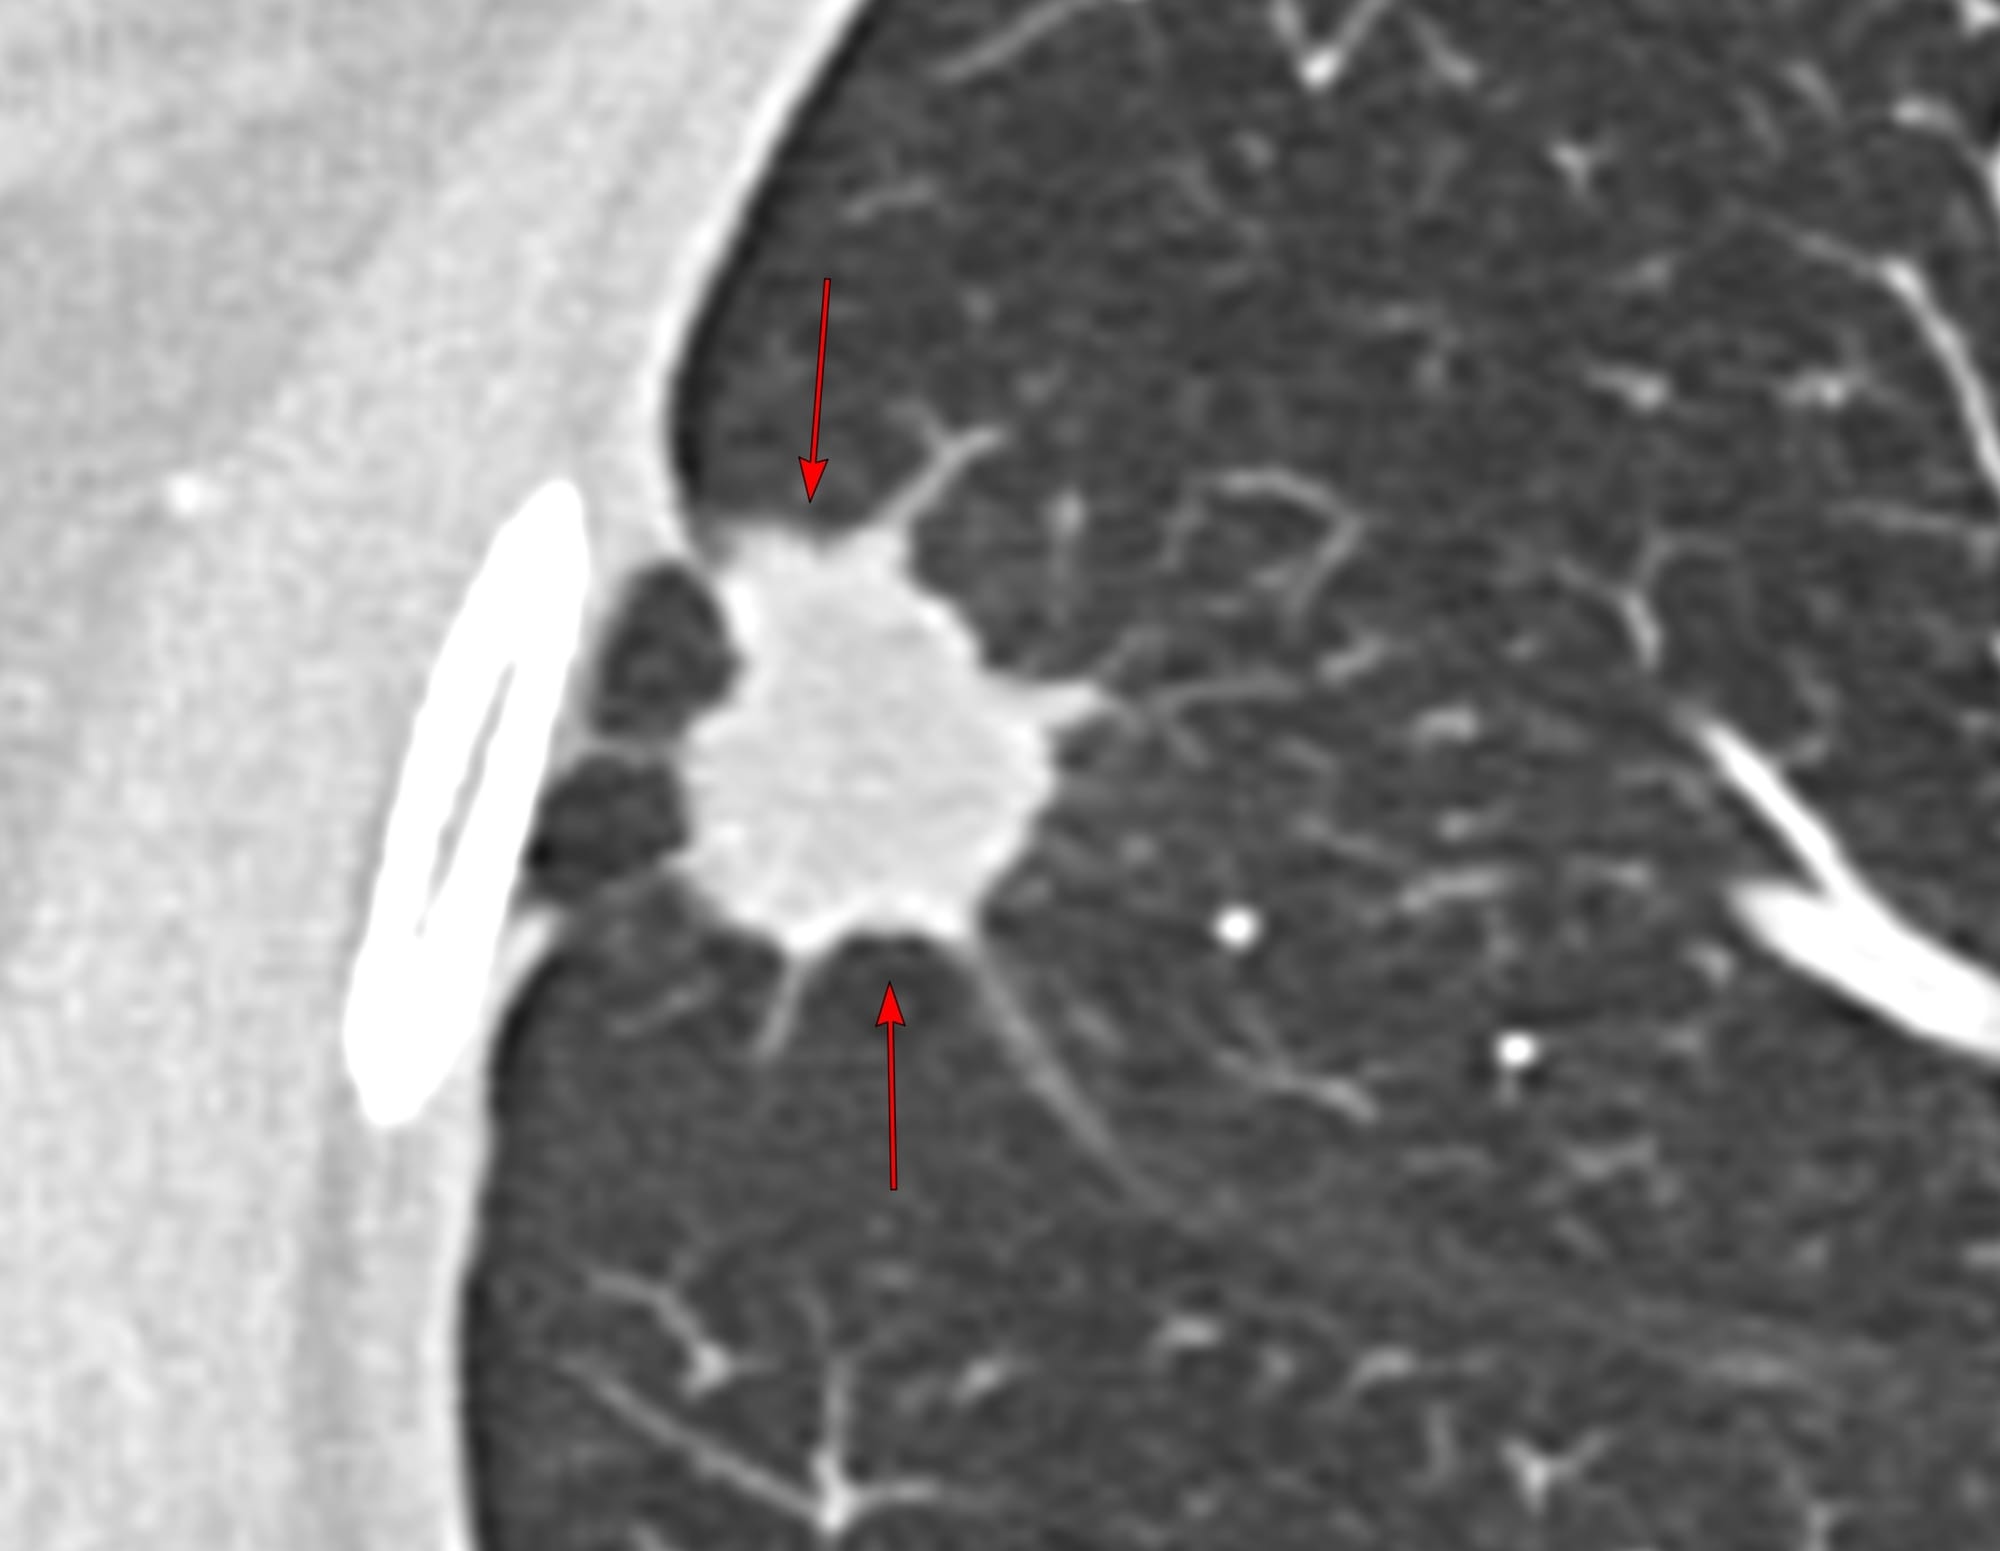

Post 06 - Signs of Visceral Pleural Invasion in a Lung Nodule - Jellyfish and Multiple Pleural Tags

These signs help diagnose visceral pleural invasion

A 44-years old was found to have a nodule in the lateral segment of the right middle lobe measuring 15.4 mm in long axis and 999 cu mm in size.

The CT guided biopsy showed adenocarcinoma.